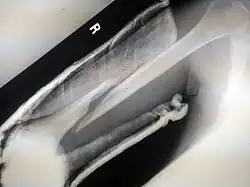

- Femoral fracture

- Hip fracture (anatomically a fracture of the femur bone and not the hip bone)

Surgical methods of treating fractures have their own risks and benefits, but usually, surgery is performed only if conservative treatment has failed, is very likely to fail, or is likely to result in a poor functional outcome.[42] With some fractures such as hip fractures (usually caused by osteoporosis), surgery is offered routinely because non-operative treatment results in prolonged immobilisation, which commonly results in complications including chest infections, pressure sores, deconditioning, deep vein thrombosis (DVT), and pulmonary embolism, which are more dangerous than surgery.[43] When a joint surface is damaged by a fracture, surgery is also commonly recommended to make an accurate anatomical reduction and restore the smoothness of the joint.